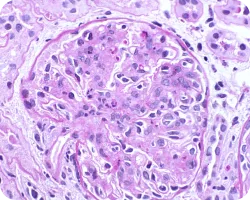

Мезангиальная пролиферация

Image

icon

Течение заболевания у пациентов с мезангиальной пролиферацией (М1) и даже низкой протеинурией ≤ 1 г/день характеризуется схожим прогнозом, как у пациентов со стойкой протеинурией от 1 до 2 грамм в день. Таким образом, несмотря на более низкую экскрецию белка, в первом случае можно говорить о более высоком риске, а также о возможной пользе более ранней иммуносупрессии, потенциально улучшающей сохранение массы нефронов42.